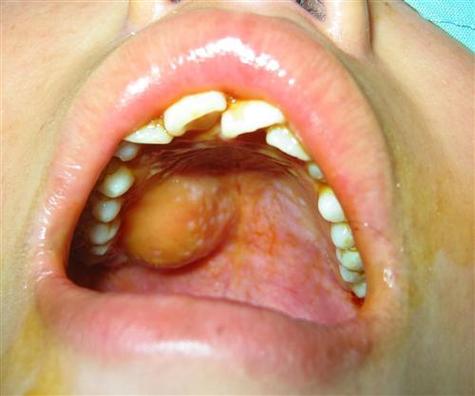

血外渗性囊肿 / 舌下囊肿 / 潴留囊肿(口外型)

这是一种特殊的囊肿,常见于婴幼儿和青少年,是由于外伤导致血管破裂,血液进入组织间隙并被包裹形成的。

- 典型外观(图片描述):

- 大小: 生长迅速,可形成较大囊肿。

- 形状: 柔软、有波动感。

- 颜色: 早期可能呈蓝色(因含血液),后期因血液分解而呈淡黄色。

- 位置: 最常见于口底,常表现为从一侧颌下区突出,形成所谓的“蛤蟆肿”。

- 感觉: 柔软,像水一样晃动,巨大时可影响呼吸和吞咽。

- 图片示例描述:

一张婴幼儿或青少年的面部照片,可以看到一侧的颌下区(下巴下方)明显不对称地鼓起一个大的、柔软的包,颜色可能是淡紫色或正常肤色,如果从口腔内看,口底一侧也会被一个巨大的、光滑的囊肿顶起,将舌头推向对侧。